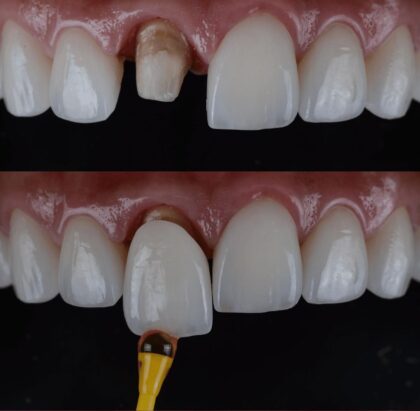

I Nostri Risultati